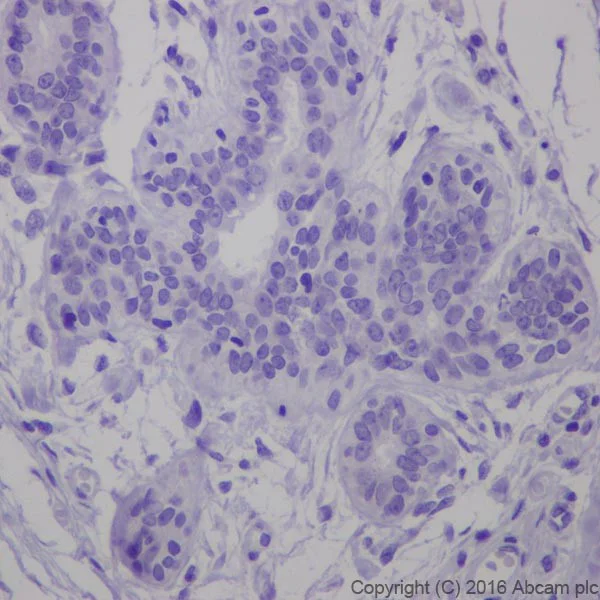

Immunohistochemistry (Formalin/PFA-fixed paraffin-embedded sections) - Anti-ErbB2 / HER2 antibody [EPR19547-12] - BSA and Azide free (AB222482)

Immunohistochemical analysis of paraffin-embedded Human breast cancer tissue labeling ErbB 2 with ab214275 at 1/4000 dilution, followed by Goat Anti-Rabbit IgG H&L (HRP) (ab97051) at 1/500 dilution.

Membrane staining on Human breast cancer is observed [PMID : 18437174].

Counter stained with Hematoxylin.

Secondary antibody only control : Used PBS instead of primary antibody, secondary antibody is ab97051 at 1/500 dilution.

This data was developed using the same antibody clone in a different buffer formulation containing PBS, BSA, glycerol, and sodium azide (ab214275).

Perform heat mediated antigen retrieval with Tris/EDTA buffer pH 9.0 before commencing with IHC staining protocol.